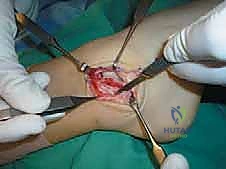

يقوم أ.د. محمد هطيف بعمل شق جراحي صغير ودقيق (حوالي 4-5 سم) على شكل حرف J أو شق منحني خلف وأسفل العظمة البارزة في الكاحل (Lateral Malleolus). يتم استخدام تقنيات الجراحة الميكروسكوبية للحفاظ على الأعصاب السطحية (مثل العصب الشظوي السطحي) والأوعية الدموية الدقيقة.

الخطوة الثالثة: تقييم التمزق وتنظيف المفصل

بمجرد الوصول إلى الكبسولة المفصلية، يتم فتحها لتقييم حالة الأربطة (ATFL و CFL). غالباً ما تكون الأربطة متندبة ومطاطية وغير قادرة على شد المفصل. يتم تنظيف أي أنسجة ملتهبة أو بقايا غضروفية حرة داخل المفصل لضمان عدم وجود ألم بعد العملية.

الخطوة الخامسة: زراعة خطاطيف الخياطة (Suture Anchors)

هنا تتجلى التقنيات الحديثة. بدلاً من حفر ثقوب كبيرة في العظم كما كان يحدث قديماً، يستخدم أ.د. محمد هطيف خطاطيف دقيقة جداً (Suture Anchors) مصنوعة من مواد متوافقة حيوياً (Bio-composite) أو التيتانيوم. يتم زرع خطاف أو خطافين في عظمة الشظية، وتكون هذه الخطاطيف محملة بخيوط جراحية فائقة القوة.

الخطوة السادسة: خياطة وشد الأربطة (إجراء بروسترم الأساسي)

يتم تمرير الخيوط الجراحية القوية عبر الأربطة الممزقة (ATFL و CFL) والكبسولة المفصلية. أثناء عقد هذه الخيوط، يتم وضع الكاحل في وضعية الانقلاب الخارجي (Eversion) والانعطاف الظهري (Dorsiflexion) لضمان شد الأربطة بأقصى درجة ممكنة، مما يعيد للكاحل ثباته الفوري.

الخطوة السابعة: تعديل جولد (The Gould Modification) - سر القوة الإضافية

لضمان عدم تكرار التمزق، خاصة للرياضيين، يضيف الجراح خطوة "تعديل جولد". تتمثل هذه الخطوة في سحب جزء من النسيج الليفي القوي المجاور والمسمى بـ "القيد الباسط السفلي" (Inferior Extensor Retinaculum) وخياطته فوق الأربطة التي تم إصلاحها. يعمل هذا النسيج كـ "حزام أمان" إضاف